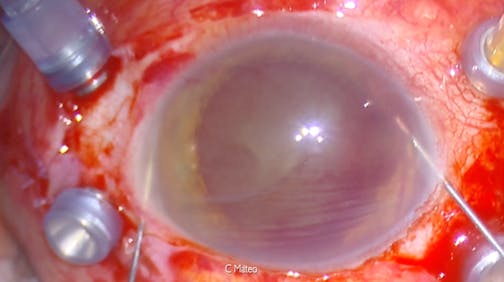

Optic Nerve Pit

Kourous A. Rezaei, MD